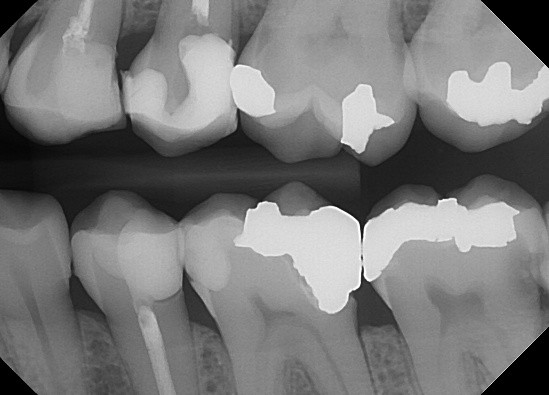

1. (Select ONE OR MORE correct answers)

The radiograph shows evidence of

2. (Select ONE OR MORE correct answers)